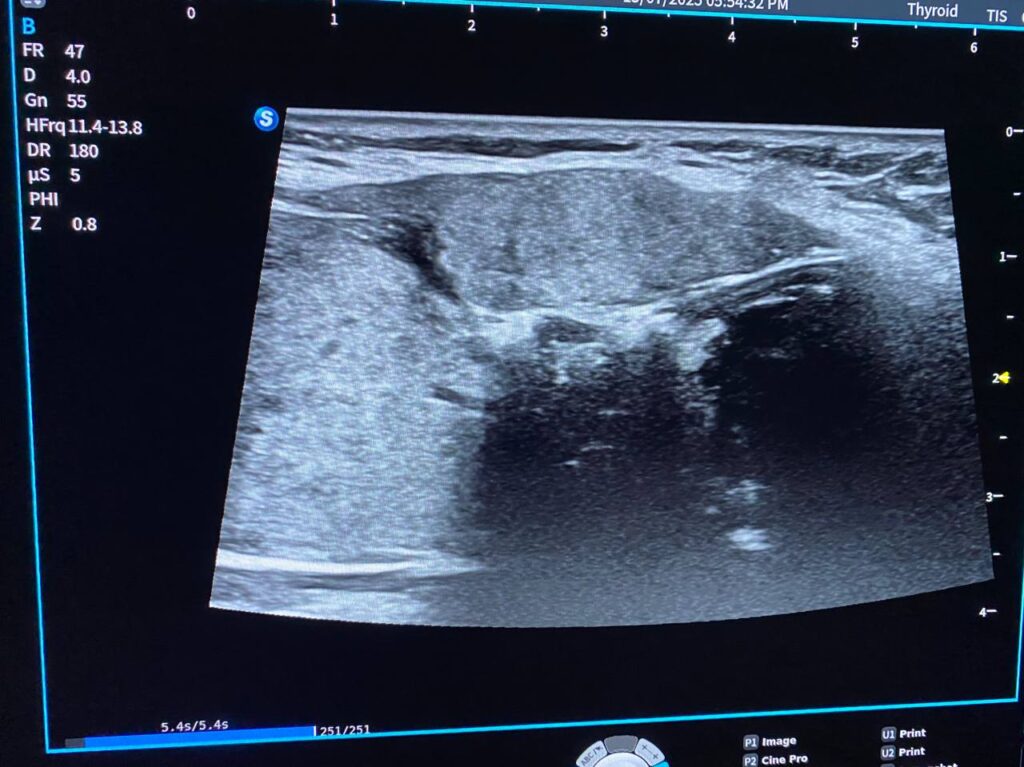

Thyroid U\S

Right lobe = 31x61x25mm

Left lobe = 24x60x20mm

Isthmus = 12mm, contain benign look nodule , its size 17x11mm

The gland diffusely has lobulated outline, geographic heterogenous multiple hypo-echoic areas, ill-defined nodules < 3mm in sizes, with inter-digitating fibrosis, interrupted capsule, Picture of Hashimoto’s thyroiditis , left lobe contain ill distinct margin mass , its size 18.5×15.5mm, bulging the capsule , with irregular lateral margin , vascular on color Doppler , contain microcalcification , other two adjacent hypoechoic irregular masses are seen 11.8×7.8mm (also contain microcalcifications) & 4.7×3.8mm , all are mostly suspicious TIRADS 4 , please for further study